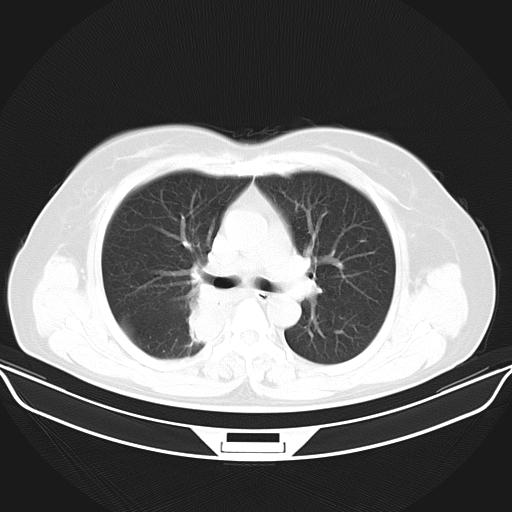

标题: CT22224:肺部肿块

f,48,主因咳嗽咳血来我院检查,无发热。

1)右肺下叶背段团块状软组织密度影;建议抗炎治疗后复查排除肿瘤性病变。2)右侧少量胸腔积液。

谈一谈个人的看法:机器性能应该不错,可惜扫描方法不太正确,即没有及时薄层扫描图像,也没有增强检查,这样的检查方法不正确的图片拿来研究只能是猜一猜:右肺下叶阻塞性改变,建议进一步检查删除肺癌。

支气管镜检查未见异性细胞,抗炎治疗20天,肿块明显缩小。